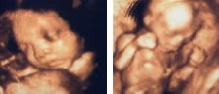

超音波検査について

当院では、平成13年に北陸で初めて、全国で7番目に導入された4D超音波診断装置で、胎児の状態をリアルタイムの3次元動画像として提供しています。